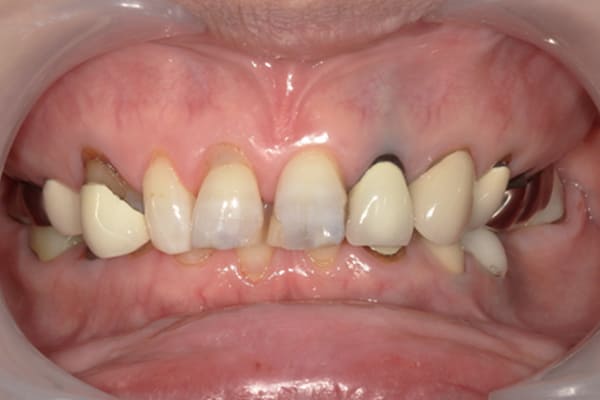

症例レポート[CASE.04]

前歯がとれて痛い、

食事もできず、見た目も悪い

- 性別・年齢

- 女性(60代)

- 主訴

- 前歯がとれて、痛い、食事ができない、見た目が悪く人に会えないので何とかしてほしい

- 治療

-

- 上顎精密金属総入れ歯

- 下顎精密金属部分入れ歯

- 磁性アタッチメント(白金加金) 1歯

- 治療期間

- 約5か月間

- 費用

- 上顎精密金属床総入れ歯:55万円

- 下顎精密金属床部分入れ歯:55万円

- 磁性アタッチメント:11万円×1歯

(白金加金)

合計:121万円(税込)

上前歯はブリッジの差し歯により根が折れ炎症を起こしお痛みのある状態でした。

原因は長期使用により下の義歯の歯が削れたことにより、下前歯が上前歯を突き上げ強い力が加わっていたことが根本的な原因と考えられます。

治療前は、奥歯が下がり、かみ合わせが乱れています。適切な入れ歯はそのままのかみ合わせで義歯を作るのではなく治療後のように、前歯から奥歯までのラインが真っすぐ揃った、かみ合わせの面を適切に付与し、よく咬め、残りの歯に負担がかからないかみ合わせとしました。

とにかく何も食べられないこと、人に会えないことから、なるべく早く何とかしたいとのご希望でした。

患者様とご相談の上、まず早急に上記を回復させるため、初診含め3度の来院でお食事ができ、見た目を回復できるように治療用義歯を作製、装着しました。

本来は、数本の上前歯の折れてしまって残せない歯は抜いてから歯肉の治癒を待ち、数か月後に型どりから作製になりますが、抜歯即時義歯といって、歯を抜く前に型、かみ合わせをとり、抜歯を行ったその日に上下の義歯を装着する特殊な治療法を用いたことで、10日後には治療用義歯をお口に装着することができ、お痛みもなくお食事ができ、ご友人とのお食事にも行けることが可能になりました。

本来、入れ歯作製は技工所と言って、義歯を作製する所に発送するため、作製には時間がかかりますが、院内に技工専用スペースを完備しており、長年、義歯治療において、技工も技術の習得してきましたので技工士さんではなく、かみ合わせの道具も私自身で院内で作製したことで、初診日の次の日にご来院いただきかみ合わせを採ることで、診断、型どり、かみ合わせ、装着まで10日という最短のご希望にこたえらた方です。